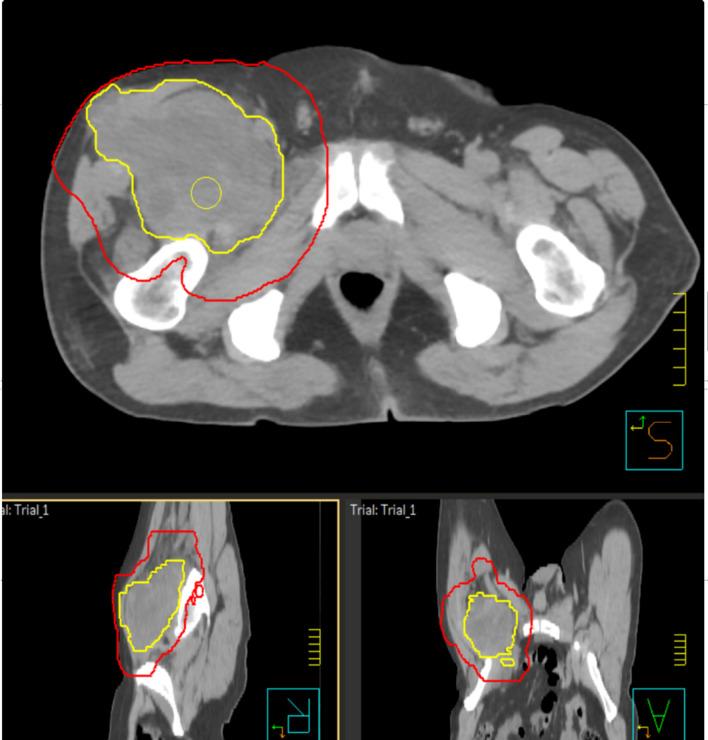

四肢成人软组织肉瘤的放射治疗作用。

The role of radiotherapy in adult soft tissues sarcoma of the extremities.

Local management of adult soft tissue sarcoma of the extremities has evolved over the past decades. Until the 1970s, radical surgery (amputations) was the standard therapeutic procedure resulting in significant physical and psychological morbidity for the patients. In the present era, limb sparing surgery combined with radiotherapy represents the current standard of care for high grade and > 5 cm STSs. This approach guarantees high local control rate and function preservation. The aim of this paper is to summarize the current evidence for RT in STSs of the extremities. Outcomes, technical details (techniques, timing, dose, volumes of treatment) and the emerging role of RT in the management of oligometastatic disease will be analysed. Finally, results of the recent clinical trials testing new scenarios in RT of STSs will be described.

在过去几十年中,四肢成人软组织肉瘤的局部治疗方法已经发生了演变。直到 20 世纪 70 年代,激进的手术(截肢)仍是标准的治疗方法,这给患者带来了显著的身体和心理上的发病率。在当今时代,保肢手术联合放疗是高级别和> 5 cm STS 的当前治疗标准。这种方法可保证高局部控制率和功能保留。本文旨在总结当前 RT 在四肢软组织肉瘤中的证据。将分析治疗结果、技术细节(技术、时机、剂量、治疗体积)以及 RT 在寡转移疾病治疗中的新作用。最后,将描述最近测试 STS 中 RT 新方案的临床试验结果。